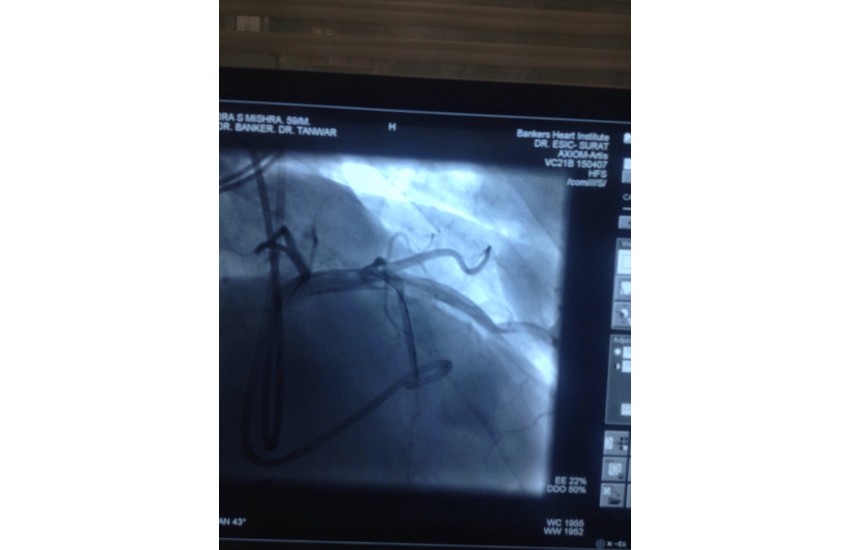

CAG revealed normal coronaries,holter shows sinus bradycardia,RBBB with LAHB,intermittent AF, TMT shows blunted chronotropic response and hypotensive response so he has been planned for PPI with back up of pacemaker patient treated with beta blockers and corderone,after 7 days of PPI,he has undergone alcohol septal ablation successfully,prior his dynaemic gradient was 50 mmhg in rest n 80 mmhg with exercise which reduced to 20mmhg after procedure. Now patient is under close follow up so will continue updating.